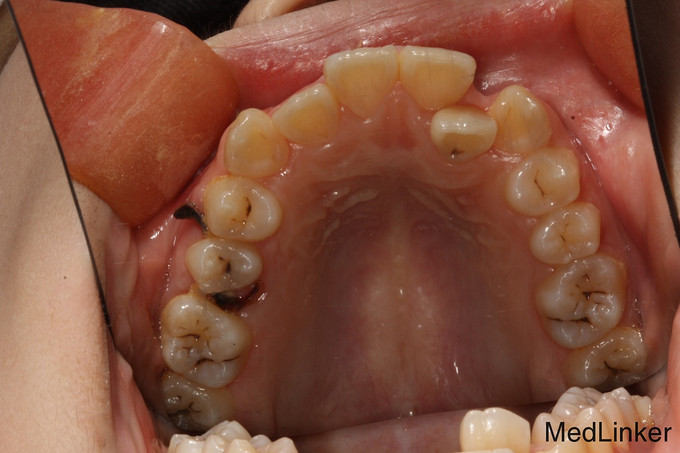

儿童牙齿矫正

14岁儿童,因牙齿生长缺陷牙列不齐,影响美观需矫正。